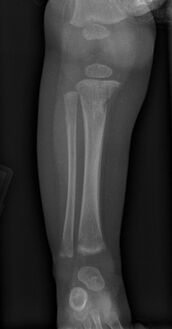

Wimberger corner sign; X-rays of (a) lower limbs (AP view) and (b) upper limbs (AP view) showing resolution of metaphyseal erosions and periosteal reaction

a) X-ray of the lower limb (AP view) showing proximal tibial metaphyseal erosions along with periosteal reaction and (b) X-ray of the upper limb (AP view) showing distal tibial and fibular metaphyseal erosions with periosteal reaction